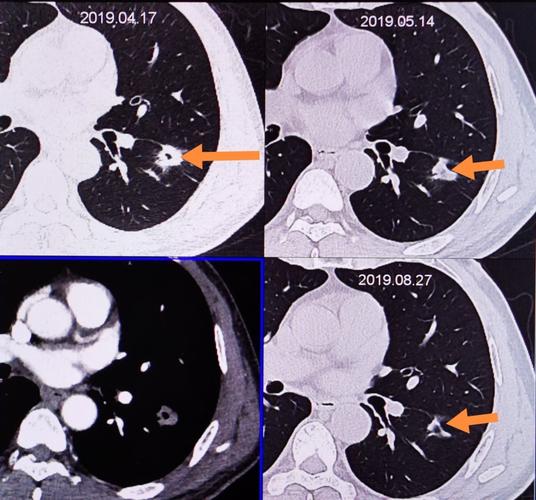

男性,吸烟多年,反复咳嗽,查胸部ct左肺占位,查气管镜确诊鳞癌

首先,展示一张肺部ct图像,从直观上介绍一下